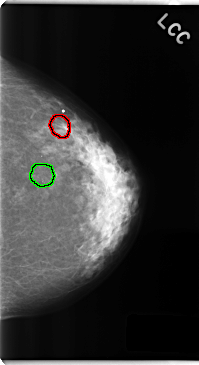

FILE: C_0247_1.RIGHT_CC.OVERLAY

TOTAL_ABNORMALITIES 1

ABNORMALITY 1

LESION_TYPE MASS SHAPE LOBULATED MARGINS ILL_DEFINED

ASSESSMENT 3

SUBTLETY 3

PATHOLOGY BENIGN

TOTAL_OUTLINES 1

BOUNDARY